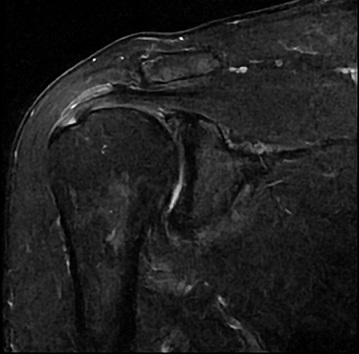

An 80 year old female presents to your office with a left ring finger deformity after a fall one week ago. She initially went to urgent care and xrays were unremarkable for a fracture (Figures 1 and 2). A photo of her left ring finger is shown in figure 3. On physical exam the left ring finger is in hyperextension at the PIP joint and flexion at the DIP joint. She able to flex her PIP joint with full motion. What is the best treatment option?